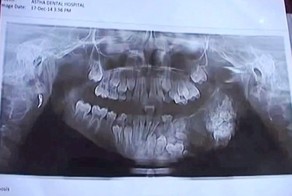

- Мальчик по прозвищу "Челюсти"

- Семилетнему мальчику удалили 80 зубов